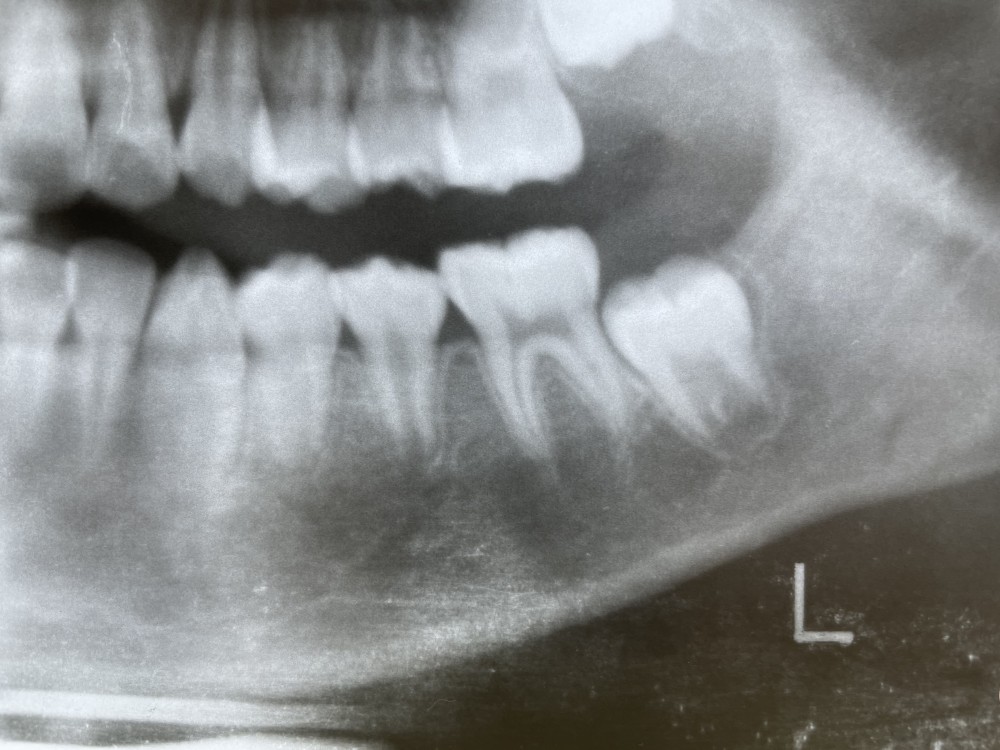

下が抜歯から1年後、10才10ヶ月のエックス線写真です。

左下5の萌出が確認できます。